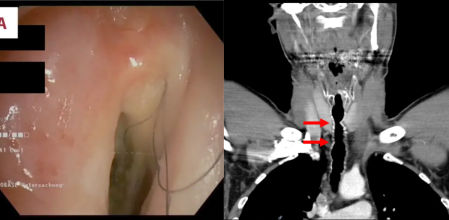

La imagen de la izquierda muestra pelo en la garganta: la de la derecha, el lugar en el que apareció el pelo.

El hombre de 52 años, cuya identidad no ha sido revelada, visitó a los médicos en 2007, aproximadamente 17 años después de comenzar a fumar. Experimentaba una voz ronca, dificultad para respirar y una tos crónica. Una broncoscopia reveló inflamación y varios pelos en la garganta, en una zona que había sido operada anteriormente. El hombre fue diagnosticado con crecimiento de pelo endotraqueal. A los 10 años, casi se ahogó y fue tratado con una traqueotomía para estabilizar su respiración. La herida fue cerrada utilizando piel y cartílago de su oreja. Posteriormente, cuando buscó tratamiento por su tos y dificultad para respirar, se detectó crecimiento de pelo alrededor del sitio de este injerto.

Los médicos lograron eliminar los pelos arrancándolos, un procedimiento que proporcionó alivio pero no una solución permanente. Los pelos continuaron creciendo y el paciente regresó al hospital anualmente durante 14 años, quejándose de los mismos síntomas. Normalmente, había de seis a nueve pelos de aproximadamente 5 centímetros en la garganta del hombre, algunos de los cuales atravesaban su caja de voz y crecían hacia su boca.